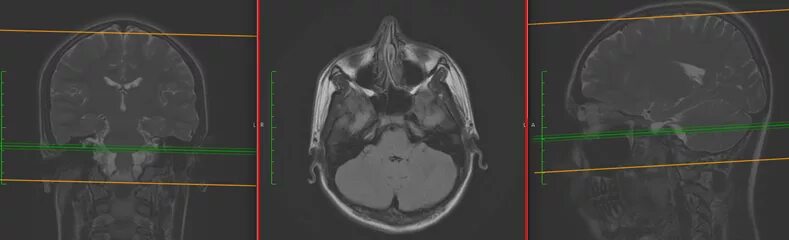

Какой программой открыть кт